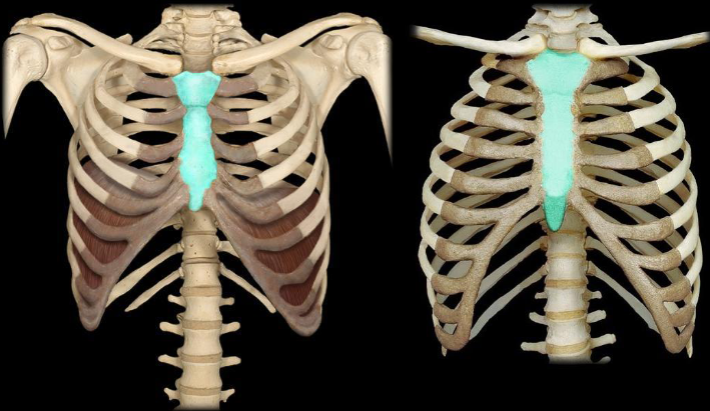

What bone is highlighted in this image?

sternum

What part of the sternum is highlighted in this image?

body of the sternum (longer part)

What part of the sternum is highlighted in this image?

manubrium (smaller & pentagon shaped)

What part of the sternum is highlighted in this image?

xiphoid process (tip)